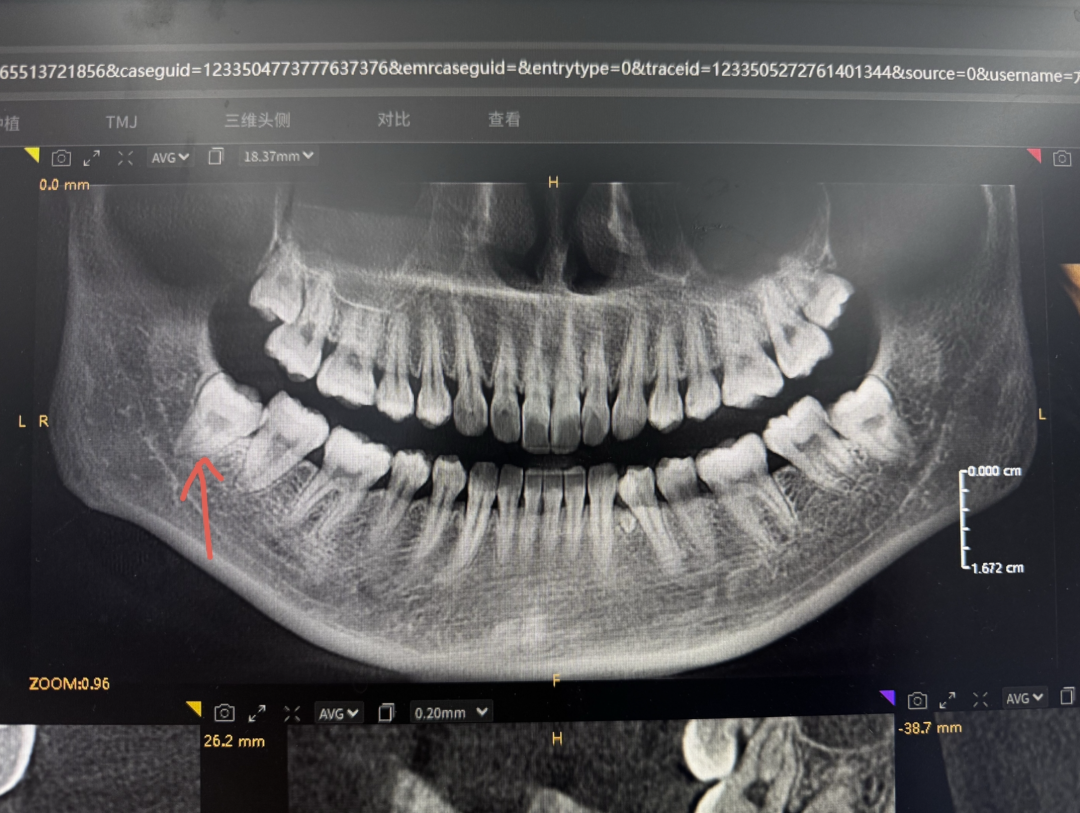

上图这种智齿很艰难的萌出,因为空间不足明显顶着第二恒磨牙长,这会引发第二恒磨牙的健康出现问题,并因为中间存在空隙导致容易堆积食物残渣难以清洁到位引发蛀牙问题等,甚至冠周炎都有一个专门的分类叫智齿冠周炎。

但不要觉得上图这种智齿是很严重的,相反那是最轻的,好歹都算萌出了,没办法萌出的智齿一大堆,甚至因为空间不足导致横着长的都有,生长目标十分明确的对准第二恒磨牙的牙根,不把宝贵的第二恒磨牙顶死誓不罢休。